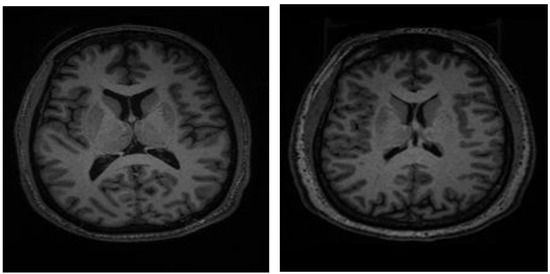

2.3. Methods Overview

To integrate the T1-weighted MR images into the ResNet50 architecture, they were uniformly resized to 224 × 224 pixels. Figure 1 illustrates representative MR images acquired from SCH and BD patients. While the T1-weighted MR volumes encompassed 216 axial slices per participant, our analysis focused on the central 32 slices to optimize computational efficiency and maintain image quality. Subsequent to slice selection, all images underwent normalization to standardize intensity values. To mitigate overfitting, data augmentation techniques were employed, carefully considering the reliability of medical images. Specifically, rotation and brightness adjustments were incorporated into the augmentation pipeline, ensuring that the generated images remained consistent with the characteristics of real MR scans. Finally, all images were scaled to a range of 0 to 1 for numerical compatibility within the neural network.

Figure 1. 224 × 224 resized MR images of patients with bipolar disorder (left) and schizophrenia (right).

Applsci 15 01717 g001